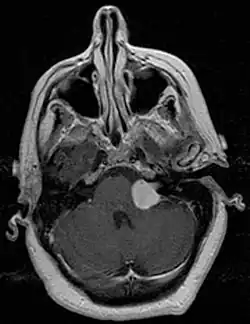

MRI scan is the imaging of choice because it can more accurately differentiate the mass from other tumors such as meningioma, facial nerve schwannoma, epidermoid cyst, arachnoid cyst, aneurysm, and brain metastasis. MRI scan also helps in surgical planning and follow-up of the tumor after surgery.[19] VS is usually isointense on T1 weighted images, hyperintense on T2 weighted images, and enhances after given gadolinium contrast.[20]

There have been cases of tumors that were actually asymptomatic until very large and at a critical stage. Tumor growth rates are highly variable: some small VSs (perhaps 50%) do not grow at all; some few grow for a time and then shrink; some appear dormant but suddenly grow rapidly. In general, although studies differ, VSs that grow are slow-growing at an average rate of 1.2 to 1.9 mm per year. IAC tumors that grow beyond 1.5 cm in diameter expand into the relatively empty space of the cerebellopontine angle, taking on the characteristic 'ice-cream-cone' appearance seen on MRIs. As 'space-occupying-lesions,' the tumors can reach 3 to 4 cm or more in size and infringe on the facial nerve (facial expression) and trigeminal nerve (facial sensation). Advanced hearing loss and spells of true vertigo may occur. Very large tumors are life-threatening when they press on the cerebellum or cause brainstem compression. Late symptoms of very large VS include headache, nausea, vomiting, sleepiness, mental confusion and eventually coma.[3][4]